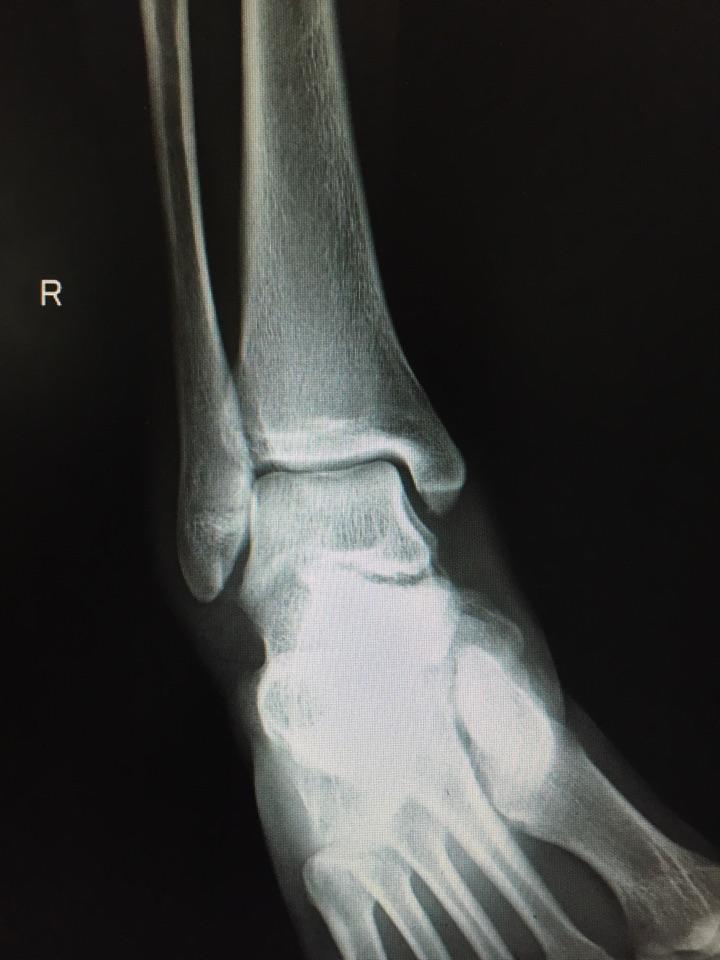

右外踝腓骨远端骨折康复记录